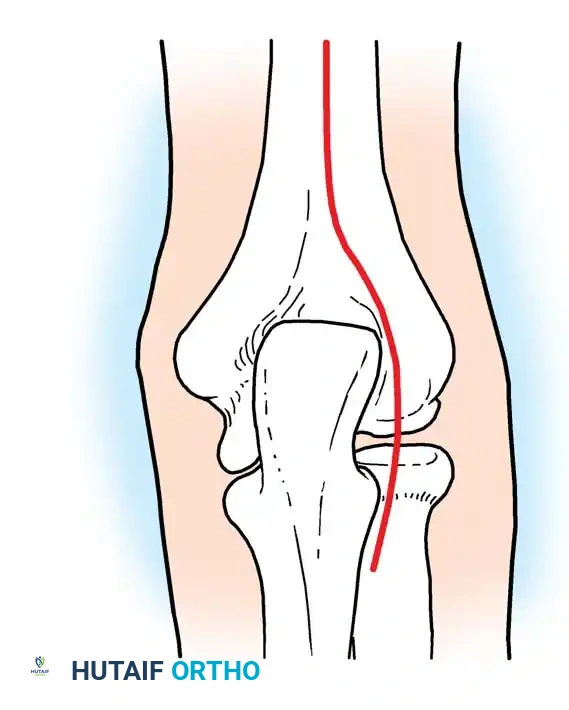

Anatomical Pitfall: During percutaneous reduction, the Kirschner wire must be introduced on the ulnar side of the radius. Introducing the wire laterally risks iatrogenic injury to the deep branch of the radial nerve (posterior interosseous nerve) as it traverses the arcade of Frohse.

Fig. 33-43 Radial neck fracture in relation to arcade of Frohse.